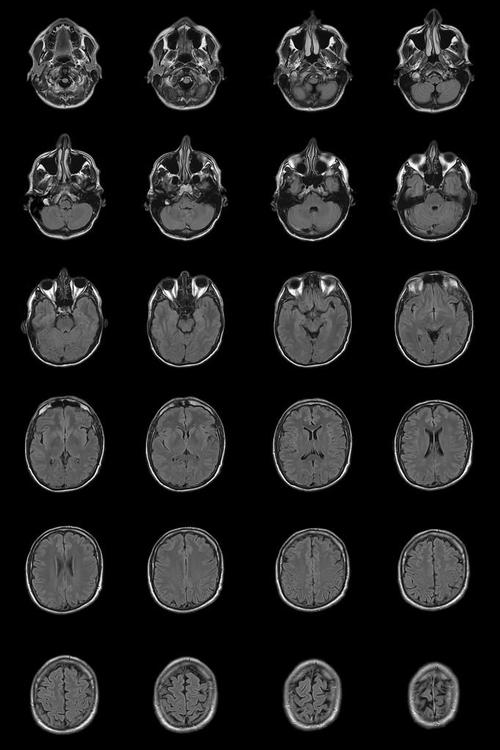

核磁共振检查新生儿脑改变有何临床意义及诊断价值?-第2张图片-郑州医学网

(图片来源网络,侵删)

• 表现:主要位于侧脑室壁,尤其是在尾状核头部附近,是一个细胞密集的区域。

• 意义:这是神经元和胶质细胞起源的地方,在早产儿中,这个区域血管极其脆弱,是脑室内出血最常见的来源,足月儿此区域大多已退化。

4. 开放的脑外间隙

• 表现:大脑表面与硬脑膜之间存在较宽的蛛网膜下腔,称为“脑外间隙”或“蛛网膜下腔”。

• 原因:这是正常的生理现象,反映了大脑皮层相对较小,随着大脑皮层的生长,这个间隙会逐渐变窄。

5. 生理性高信号区域

• 表现:在T1加权像上,部分脑白质、小脑齿状核、基底节等区域会出现生理性高信号。

• 原因:这些区域是髓鞘化的起点,早期即开始发育,因此在MRI上会表现为比周围组织更亮。